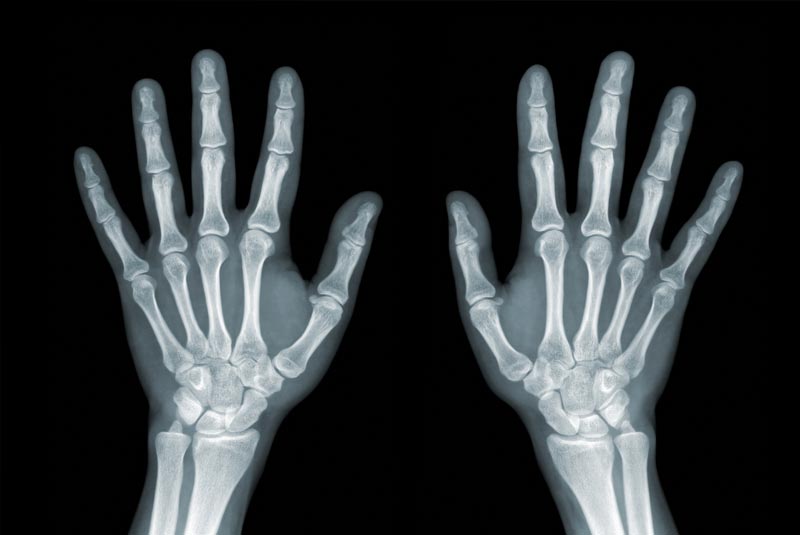

Wrist & Hand Surgery

• Open Wrist & Hand Surgery (Carpal Tunnel Release, Trigger Finger Release, De Quervain Release, Dupuytren Contracture Release, Trapeziectomy, Triangular Fibrocartilage Complex (TFCC) Repair, Tendon Repair)

• Wrist & Hand Fracture Fixation